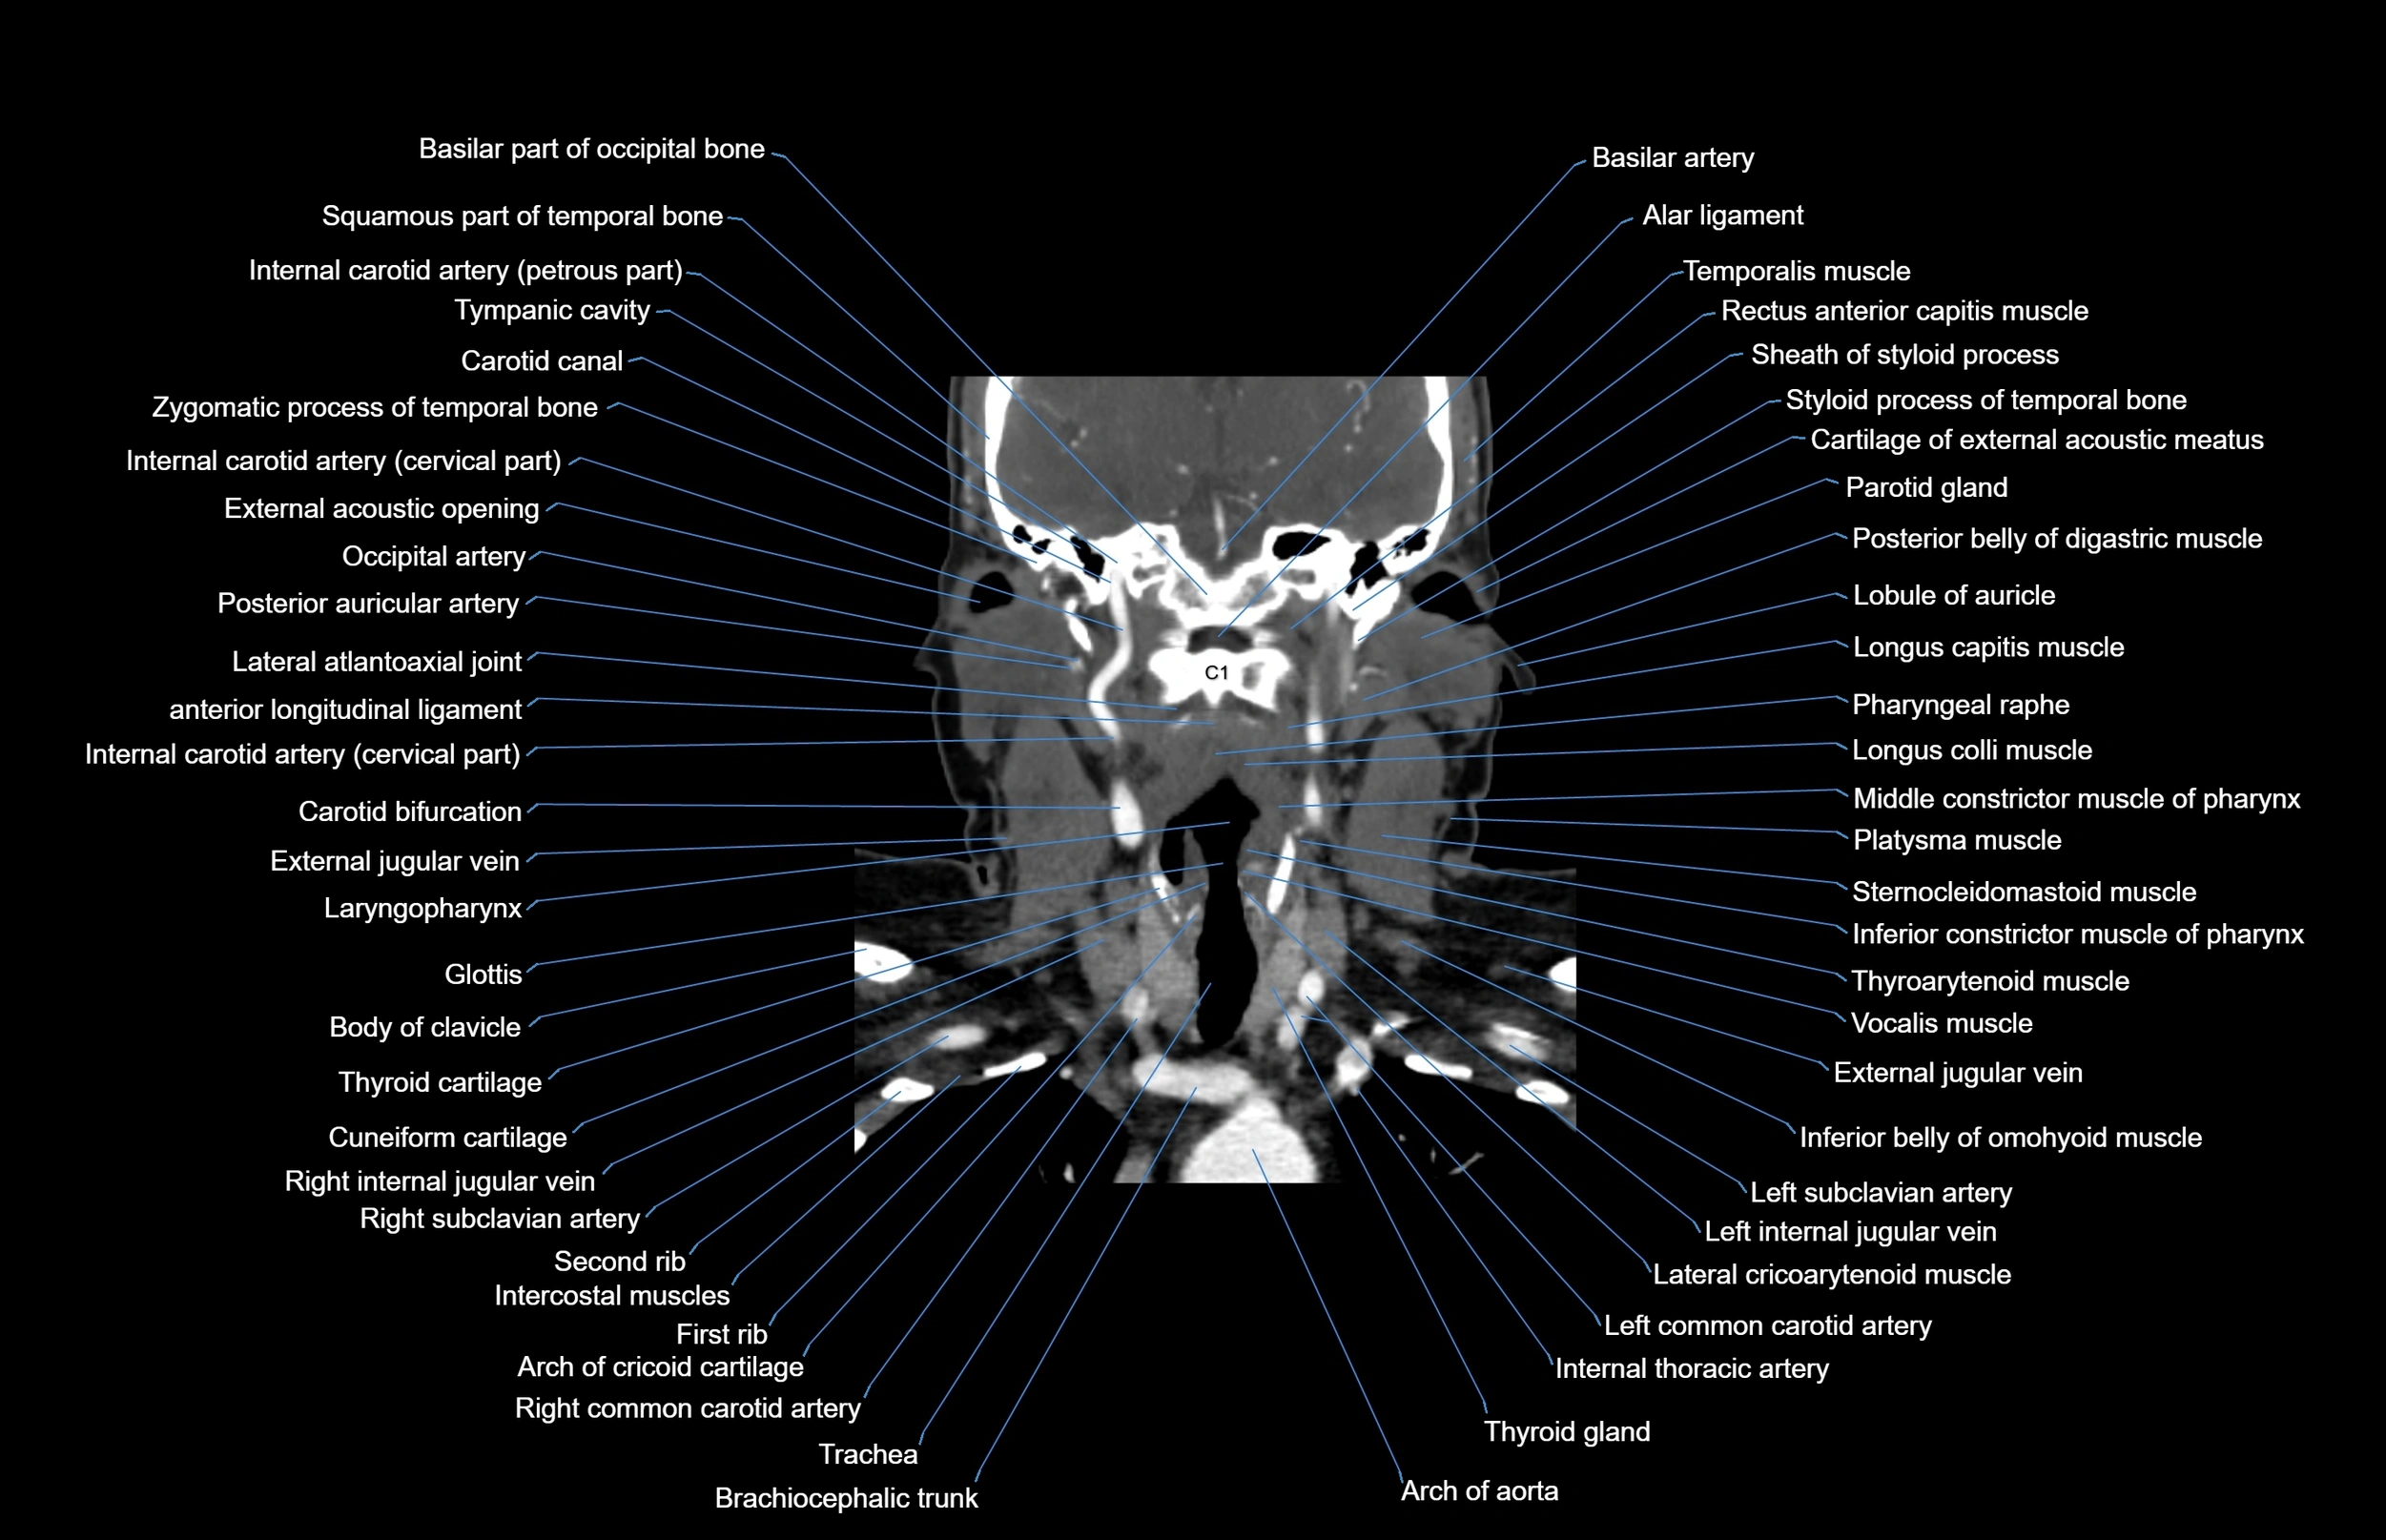

- Alar ligament

- Brachiocephalic trunk

- Carotid bifurcation

- Carotid canal

- External jugular vein

- Glottis

- Inferior constrictor muscle of pharynx

- Internal carotid artery (cervical part)

- Internal carotid artery (petrous part)

- Internal thoracic artery

- Lateral atlantoaxial joint

- Left common carotid artery

- Left subclavian artery

- Longus capitis muscle

- Longus colli muscle

- Middle constrictor muscle of pharynx

- Pharyngeal raphe

- Platysma muscle

- Sternocleidomastoid muscle

- Thoracic part of esophagus

- Thyroarytenoid muscle

- Thyroid gland

- Trachea

- Vocalis muscle

- Zygomatic process of temporal bone